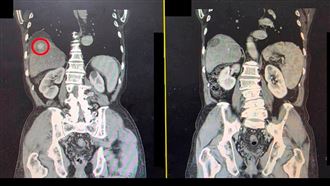

5名大學生經過高壓氧治療,已順利恢復意識。(圖非新聞當事人/大千醫院提供)

醫師表示,當發生一氧化碳中毒時,即時的高壓氧治療非常重要,高壓氧治療是讓病人在完全密閉的高壓氧艙內吸入100%純氧,以高濃度氧氣置換出體內的一氧化碳,同時改善身體組織缺氧狀況及增加細胞存活。部分一氧化碳中毒的病人,在中毒處理後的數天至數月會發生遲發性的神經後遺症,包括慢性頭痛、運動混亂、人格混亂、記憶力減退、步態不穩、視力減退等。症狀可能持續一年以上甚至終身,若能在中毒初期儘早給予高壓氧治療,就能減少對身體的傷害,也能大幅降低日後發生神經學後遺症的機率。